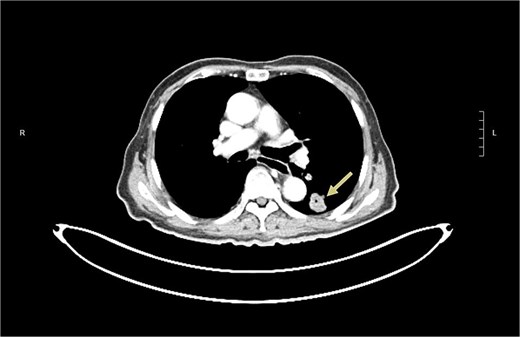

The patient was noted to have rising CEA up to 17ug/L at a time over 2 years after operation. PET CT showed a new 2.3 cm hypermetabolic lesion at lower lobe of left lung but no intra-abdominal recurrence (Fig. 7). Biopsy of lung lesion revealed mucinous adenocarcinoma, which could be lung primary or metastatic ICC. As the patient was not a candidate for lung resection, he received stereotactic body radiotherapy (SBRT) for the lung tumor. CEA gradually returned to normal afterwards and repeated CT revealed post-radiation change only at site of tumor (Fig. 8). The patient remained well ˃5 years since initial operation without evidence of further recurrent disease.